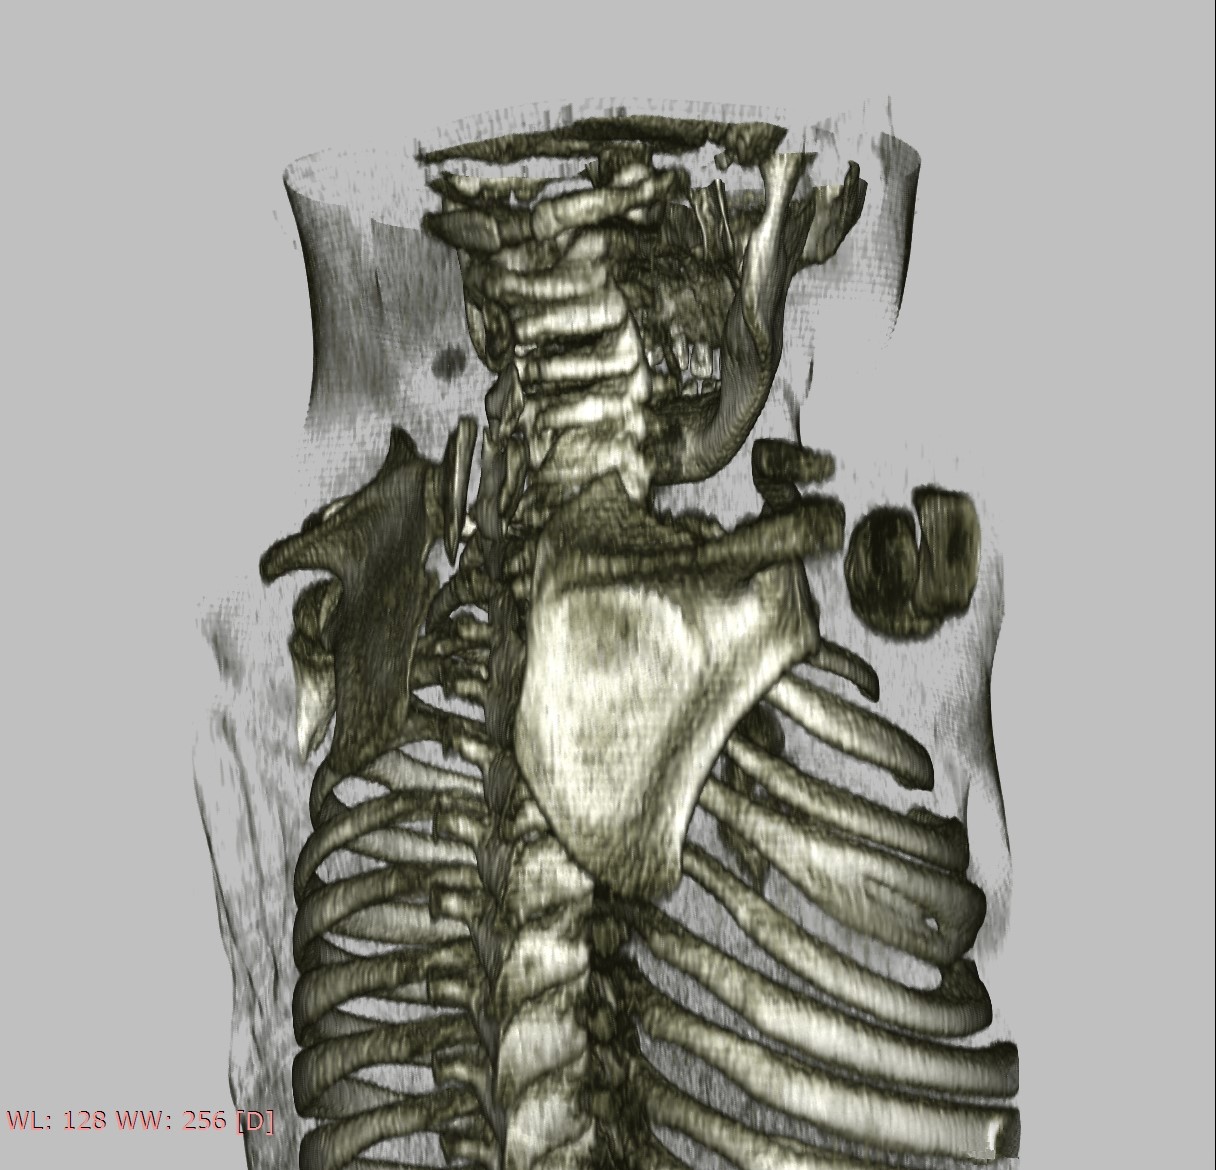

Subsequent radiographs and an ultrasound of both shoulders and scapulae and a close-up X-ray of the left shoulder revealed a fusion of costa 3 and 4. For further evaluation of the cervical spine we made a CT scan which showed a partial fusion of the vertebral corpus C5-C7 on the left and corpus Th2-Th3, Th5-Th6, a fork rib of the 4th rib on the right side (figure 2) and a different morphology of costa 7 on the right. Also seen was a bilateral Sprengel’s deformity; left grade 3 with os omovertebrale, right grade 2 (table 1), articulating with the spinous process C7 (figure 3). As a result of these findings the parents were informed about the diagnoses and the patient will be monitored by a paediatric orthopaedic surgeon until adulthood. Physiotherapy was continued with the aim of maintaining shoulder function. Clinical genetic research revealed no known associated gene mutations, but did show a sequence change in the GDF6 gene with unknown clinical consequences.

Figure 2. 3D reconstruction of CT thorax, cervical spine, shoulders.